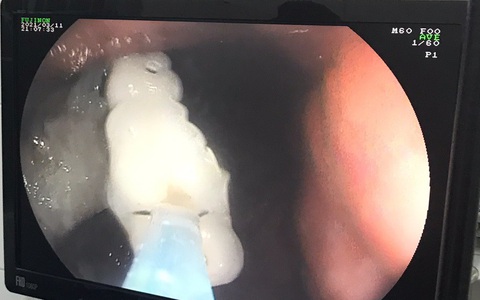

TTO - Ngày 24-5, các bác sĩ nội soi Bệnh viện Đa khoa trung ương Cần Thơ vừa thực hiện nội soi can thiệp lấy hàm răng giả 4 chiếc, bị kẹt trong phế quản một nam bệnh nhân.

TTO - Êkip nội soi Bệnh viện Đa khoa trung ương Cần Thơ vừa nội soi lấy 4 chiếc răng giả trong dạ dày một nữ bệnh nhân.

TTO - Bệnh viện Chợ Rẫy cho biết các bác sĩ tại khoa nội soi vừa gắp thành công dị vật là một chiếc răng giả trong thực quản của nam bệnh nhân 42 tuổi. Theo bệnh nhân, ông lắp răng giả cách đây khoảng 4 năm nhưng bị rơi khi nào không biết.

TT - Vội vàng ăn khuya sau một ngày làm việc vất vả, ông D.B.S. (60 tuổi, ở Q.5, TP.HCM) đã nuốt luôn bốn chiếc răng giả.